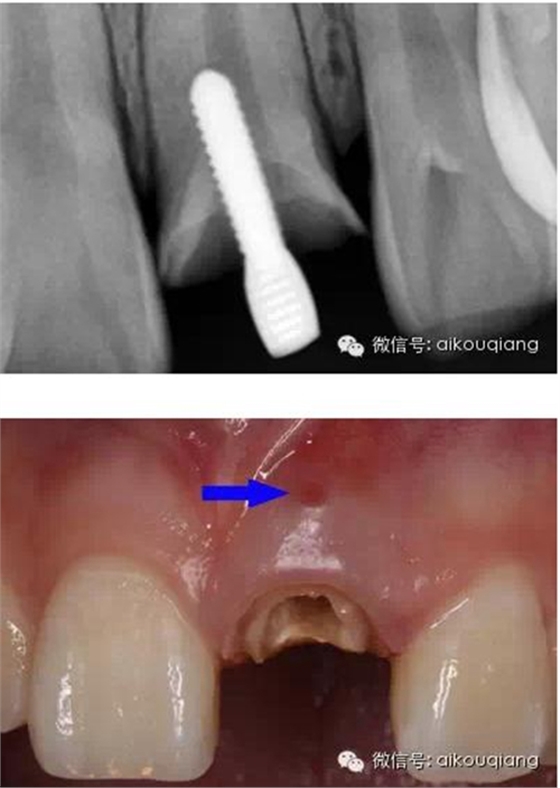

患者外院螺紋樁核加樹脂冠

唇側(cè)出現(xiàn)瘺管

X片

瘺管部位